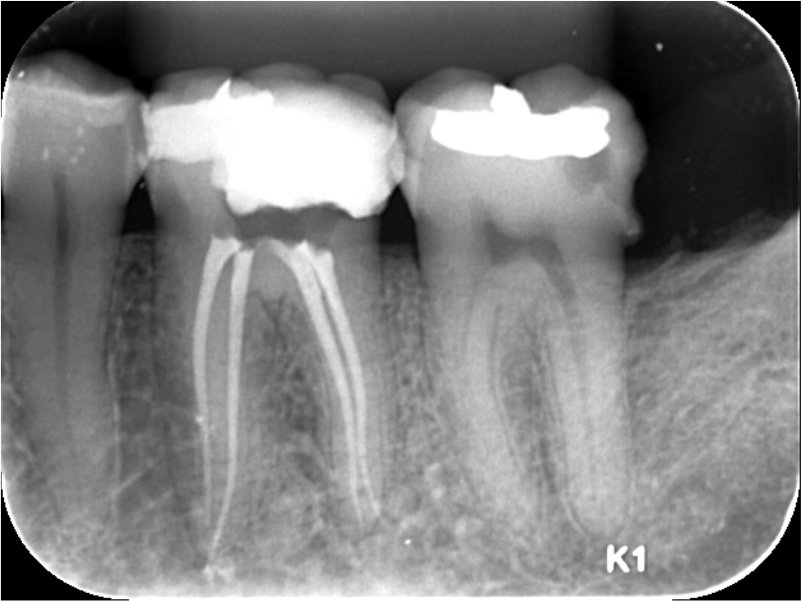

This case used the Bassi Logic 25/.03.

Xrays & Photos: